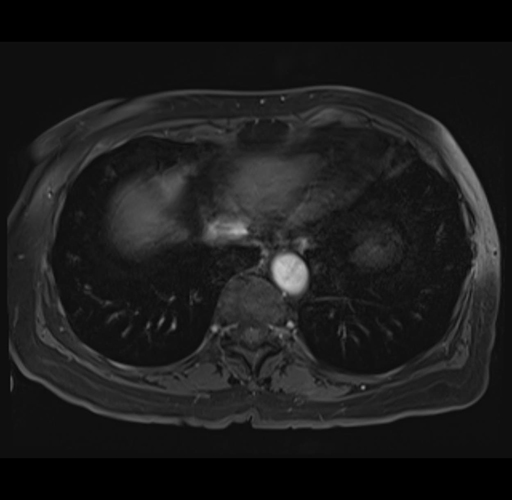

MRI T1